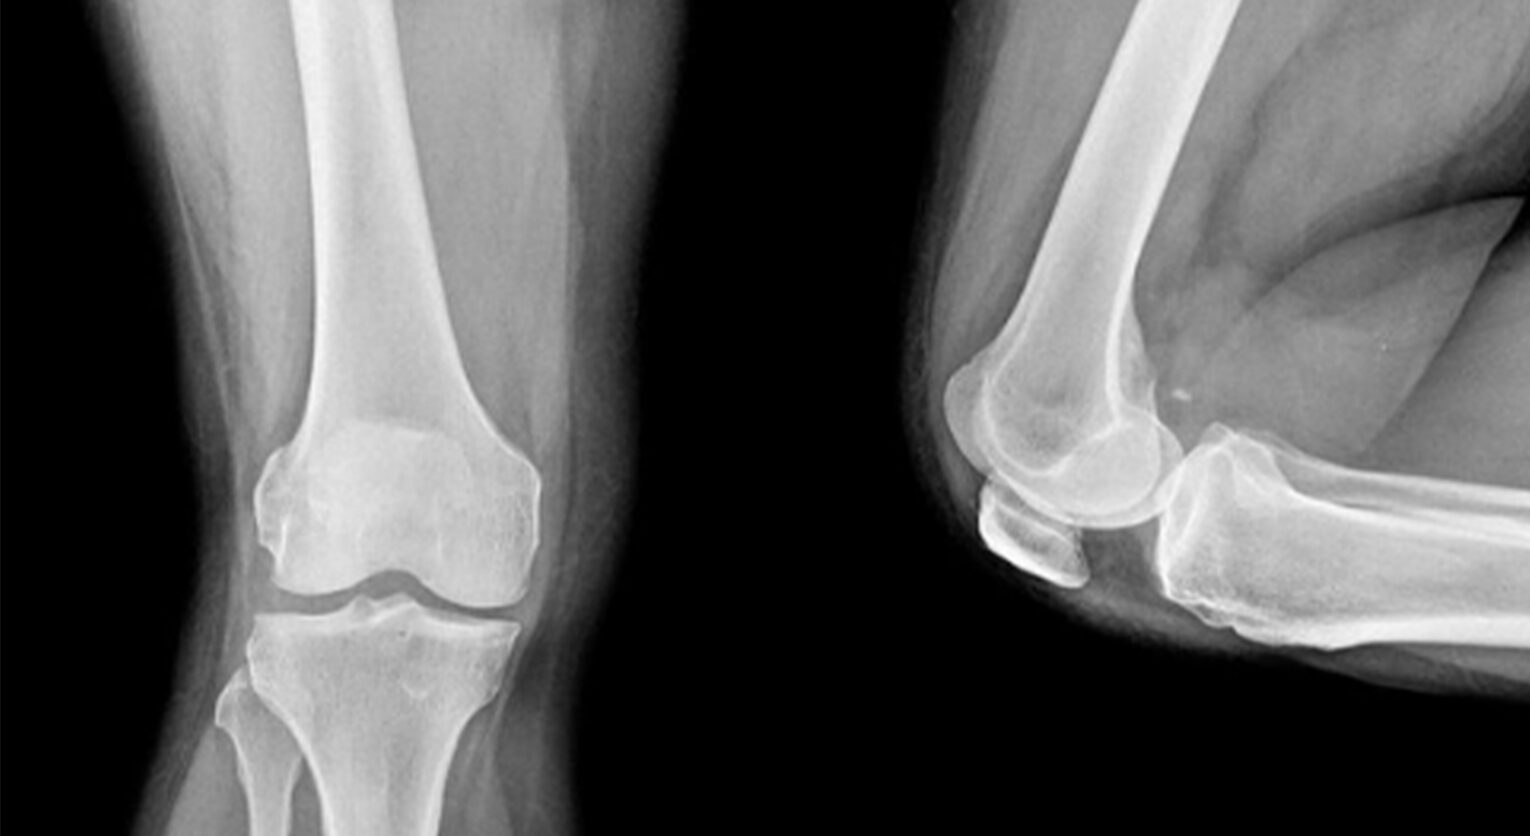

Scafoide per Frigo e rotula per Germani. La rinuncia al Tour de l’Avenir in partenza oggi è stata una decisione obbligata e maturata a quasi due settimane dalla caduta avvenuta a Sestriere dove si trovavano per il ritiro con la nazionale U23. Nelle parole di entrambi abbiamo trovato rammarico e stupore dovuto alla mancata scoperta delle rispettive fratture una volta ricevuta la prima diagnosi da radiografia (foto in apertura radiografieadomicilio). Avrebbero potuto anticipare il trattamento o l’operazione? Queste fratture invisibili, lo sono davvero o sono frutto di un’indagine offuscata dalla voglia di ritornare al più presto in sella? Per rispondere a questi dubbi ci siamo affidati a Maurizio Radi, titolare di Fisioradi Medical Center.

Attraverso la risonanza magnetica le fratture invisibili sono facilmente individuabili (foto MInihospital)

«Le fratture invisibili sulle radiografie ci sono. L’iter che si fa su un trauma – spiega – è chiaro ed efficace. Si parte con l’RX. Se questo non segnala nulla, si procede con i trattamenti delle contusioni normalmente. Se il dolore persiste o si presenta dopo qualche giorno quando si riprende l’attività, allora si effettuano accertamenti diversi per andare a vedere se c’è qualcosa che non si è visto con la radiografia. A questo punto la strada più comune è quella della risonanza, che va ad indagare in maniera mirata per fare emergere la presenza di eventuali fratture.

«Su di un trauma contusivo – spiega Radi – come può essere quello di una caduta non grave, dove il ciclista si alza e risale in bici, il primo accertamento è quello della radiografia. Il dolore seppur sia un sintomo banale è quello che però ci fa capire se la strada che abbiamo preso sia corretta o meno. Gli strumenti ci aiutano, ma la risposta del nostro fisico è la cosa più importante».